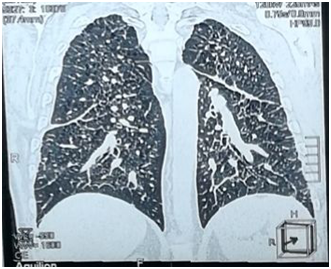

Chest Multi-Slice CTscan revealed several diffused interstitial reticular densities in both pulmonary fields with small nodular densities without enlargement of lymphatic nodes (Figure 3). Pelvis Multi-Slice CT scan revealed lytic lesions in hip and legs without invasion of adjacent tissues (Figure 4). We sent the Bronchial incisional biopsy taken by bronchoscopy and surgical incisional biopsy taken from left tibia to pathology department.

Figure 3 Chest MSCT showing several diffused interstitial reticular densities in both pulmonary fields with small nodular densities.

Pulmonary involvement is observed in 20-40% of LCH patients and can give symptoms, such as pneumothorax, dyspnea, tachypnea, and cough. Imaging studies of the lungs may reveal cysts and micronodular infiltrates.7 The patient had grade II dyspnea. CXR and MS- CT imaging of the lungs showed diffused interstitial reticular density. We performed Bronchoscopy and biopsy that showed histological features consistent with LCH.